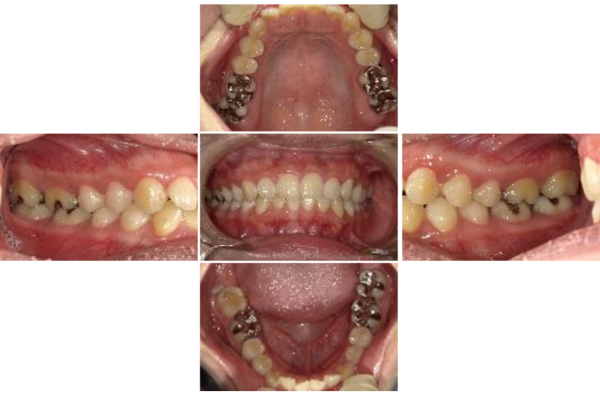

左顎関節症(開閉口時疼痛)、不随症として頭痛、左側咬合不全症

治療前

治療後

年齢・性別

20代・女性

ご相談内容

左顎関節症(開閉口時疼痛)、頭痛。ネットでこの様な症状に強いと思い来院。

治療期間・治療回数

約9か月 治療回数16回

費用

税抜332,630円

カウンセリング・診断結果

行ったご提案・治療内容

①左側の咬合不全に対し、咬合接触感を仮想として提供。

②左顎関節症(開閉口時疼痛)、頭痛が即座に消失・改善。

③この体験により左側咬合不全の改善を行う事が必要と納得。

術後の経過・現在の様子

左顎関節症(開閉口時疼痛)、頭痛で悩まなくなった。ただ、仕事柄慢性的な凝り性に陥りがちと理解(作業関連性筋痛症)。

この影響から歯牙の損傷防止の為定期的に機能回復をメインテナンスとして行う。